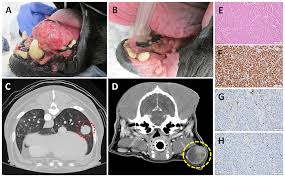

Symptoms of lung cancer in dogs include difficulty breathing, weight loss, and lethargy. Dogs with lower grade tumor had a median survival of 22 months whereas dogs with higher grade tumor had a median survival of 6 months. Secondary lung cancer is when a cancer that started somewhere else in the body has spread to the lung. Dogs who showed symptoms had a median survival of 8 months compared to 18 months in those without symptoms. Lung tumors have moderate to high potential for metastasis (spreading).

While there are treatments and methods for achieving remission or even curing cancer in dogs, each. Our canine companions are a member of our family, making a cancer diagnosis extremely devastating. So for humans, 8.3% of their lifespan is 6 years. Recurrence or spread of the tumor is a common cause of death. Metastatic cancer to the lungs is much more common than primary lung cancer. If a dog has a single primary lung tumor that has not spread to the lymph nodes, he has an average survival time of 12 months. Primary lung cancer, or tumors originating in the lung, are relatively uncommon in dogs (less than 1% of all cancers in dogs), although the number. Dogs have an average life expectancy of 12 years.

Lung cancer (adenocarcinoma) average cost. If that $5,000 could cure the cancer and restore jack's full life expectancy, maybe we'd do it. On average, lung cancer in dogs will metastize in 2 to 10 months, depending on when the tumor is detected and what treatment options are available or the strength of the animal to fight the disease. And that is with chemotherapy! In female dogs, mammary cancer also spreads to the lungs. Lung cancer is a serious disease that places both the health and well being of dogs at serious risk. The life expectancy and prognosis of a dog with lung cancer depend on tumor size, location, and metastasis. If a dog has a single primary lung tumor that has not spread to the lymph nodes, he has an average survival time of 12 months. What causes lung cancer in dogs? Lung tumors are relatively rare in dogs, accounting for only 1% of all cancers diagnosed. However, if surgery is possible and the tumors are completely removed, a total remission may be recorded. Our canine companions are a member of our family, making a cancer diagnosis extremely devastating. Life expectancy life expectancy for lung cancer in dogs can range anywhere from 2 months to nearly 2 years.

Unfortunately, some dogs diagnosed with lymphomas will not respond to treatment, and so it's important for owners to engage in open and empathetic conversations with vets. While there are treatments and methods for achieving remission or even curing cancer in dogs, each. Dogs who showed symptoms had a median survival of 8 months compared to 18 months in those without symptoms. If the lymph nodes are involved or multiple tumors are found at the time of diagnosis, survival time is shortened to only 2 months. So one year is 8.3% of life for dogs. If that $5,000 could cure the cancer and restore jack's full life expectancy, maybe we'd do it. Canine lung cancer life expectancy canine lung cancer is of 2 types: The outlook is best for dogs with a singular primary lung tumor that has not yet spread to different locations.

The goal is to spot the clinical signs of the condition as soon as possible to give your pet the best chance of survival. Lung tumors have moderate to high potential for metastasis (spreading). Life expectancy life expectancy for lung cancer in dogs can range anywhere from 2 months to nearly 2 years. Primary lung cancer, or tumors originating in the lung, are relatively uncommon in dogs (less than 1% of all cancers in dogs), although the number. Despite what research studies suggest, neither dog lived to their expected survival. Lung tumors are relatively rare in dogs, accounting for only 1% of all cancers diagnosed. Where a cancer starts is called the primary cancer. A dog with a single primary lung tumor that has not spread to the lymph nodes has the longest average survival time (an average of 12 months); This is very good news! The life expectancy of a dog diagnosed with lung cancer can be up to 22 months, depending on the type of tumor and on the treatment the dog undergoes. Our canine companions are a member of our family, making a cancer diagnosis extremely devastating. Metastic neoplasia (cancer) average cost. (here is a good link for average life expectancies.) for perspective, humans on average have a life expectancy of 72.6 years.